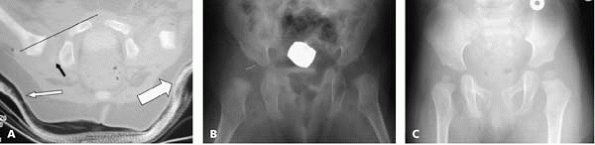

▪ FIGURE 21-8 (A)

CT scan following closed reduction and arthrogram of the right hip. The hip is located as judged by a line along the anterior cortex of the pubis intersecting the proximal femoral metaphysis (thin black line). The small black arrow demonstrates the characteristic apparent posterior subluxation of the femoral head within the acetabulum, which is present even when the hip is located. The small white arrow demonstrates mediocre molding of the cast under the greater trochanter to help keep the hip reduced. The trochanteric molding on the other hip (large white arrow) is actually better in this patient. A substantial trochanteric mold can help maintain the hip in a reduced position. (B) AP radiograph three months following closed reduction and casting. (C) AP radiograph 12 months following closed reduction. The right femoral head is smaller than the contralateral unaffected side, which may persist for a long time despite correct treatment. |

a spica cast, CT or MRI should be used to confirm reduction of the hip.

modified Shenton’s line to confirm reduction12 (Fig. 21-8). When it remains dislocated, it is usually clear (Fig. 21-9).

▪ FIGURE 21-9

CT scan following arthrogram and closed reduction of the right hip. Note that obtaining the CT scan shortly after the intraoperative arthrogram helps outline the femoral head. The right hip is dislocated as judged by a line along the anterior cortex of the pubis not intersecting the proximal femoral metaphysis (thin black line). There is no molding under the greater trochanter (white arrow). Better molding of the cast under the greater trochanter may have aided in holding the hip in a reduced position. The extreme abduction of the contralateral hip is undesirable and could result in AVN. |